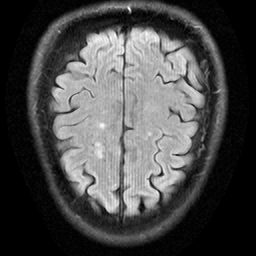

In contrast to prior work [10, 12, 13, 14], we use a single diffusion prior pθ(x)ϕ(x)subscript𝑝𝜃𝑥italic-ϕ𝑥p_{\theta}(x)\thicksim\phi(x)italic_p start_POSTSUBSCRIPT italic_θ end_POSTSUBSCRIPT ( italic_x ) ∼ italic_ϕ ( italic_x ) parameterized by θ𝜃\thetaitalic_θ, trained on a large and diverse dataset of MRI images. Our prior is trained on a diverse data distribution populated by a large collection of approximately 289,000 MR images including brain, knee, prostate and other body regions from 1.5T, 3T scanners etc. The advantage of training a diverse prior instead of ones specific to certain anatomies is that a single prior can be used across inverse problems in multiple anatomical regions (for example, knees, brain etc.). The evaluation data used for validating this and the preparation of this article, was obtained from the NYU fastMRI Initiative database [15], which is further discussed in Section 3.

We use EDM2 [16] as the backbone architecture of our diffusion priors. We train with whole images (256×256256256256\times 256256 × 256), as well as with randomly sampled patches of size 128×128128128128\times 128128 × 128 as in Patch Diffusion [17]. We also do not train with additional padding as in PaDIS, to evaluate the feasibility of patch-wise inference in generically trained models. Peak Signal-to-Noise Ratio (PSNR) and Learned Perceptual Image Patch Similarity (LPIPS) [18] are used as our metrics to measure performance. We use two inverse problems to evaluate the effectiveness of our trained diffusion priors – Denoising and Super-Resolution (2×2\times2 ×). We use both whole image (256×256256256256\times 256256 × 256) inference and at patch sizes of size 64×64646464\times 6464 × 64 and 128×128128128128\times 128128 × 128. As mentioned in Section 2.1, we use a large and diverse training set of 289,000 complex MR images. A single slice from 62 Knee and 200 Brain volumes (not included in the training data) from the NYU fastMRI Initiative database [19, 15] are used for evaluation. DPS [5] and DiffPIR [6] serve as plug-and-play approaches to solving our inverse problems.

Fig. 2: Results on Denoising (Top row) and Super-Resolution (Bottom row) tasks using DiffPIR. We demonstrate perceptually comparable performance of our diverse prior in both patch-based (DiffPIRfullfull{}_{\text{full}}start_FLOATSUBSCRIPT full end_FLOATSUBSCRIPT) and patch-based DiffPIRpatchpatch{}_{\text{patch}}start_FLOATSUBSCRIPT patch end_FLOATSUBSCRIPT training.